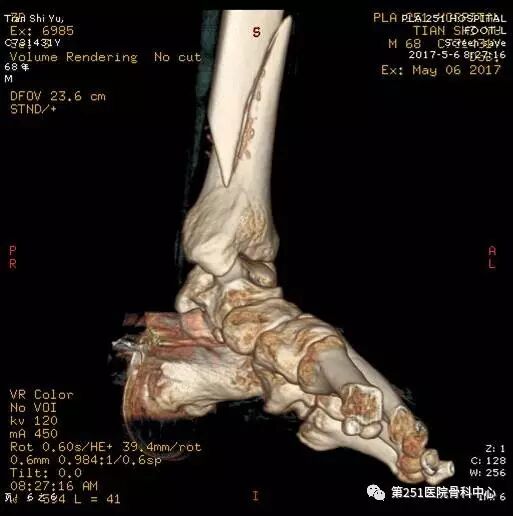

病例9:男性、68岁、车祸伤,胫腓骨远端骨折。